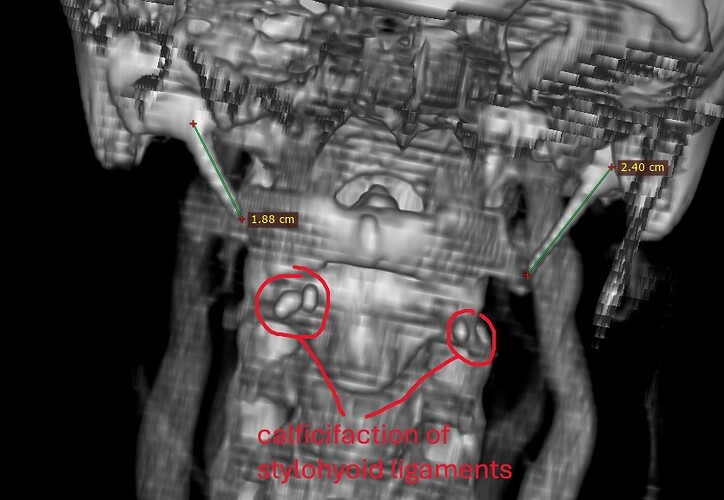

Further down, there is a pocket of calcified stylohyoid ligament on both sides. It may not look like much, but these little calcification pockets can irritated nerves.

@chrEagle I don’t have the number, and it may be hard to see in 3D. Most radiologists use the axial view (the view I posted) when assessing for compression anyway, so it may be better to just show your doctor image #3 and explain to them that you think your left ICA is compressing your left IJV (and against your posterior digastric). A surgeon can move the ICA which may be all you need IJV-wise. However, you do have those small pockets of calcified stylohyoid ligaments and I wonder if they are contributing to any symptoms. Doesn’t appear they are contributing to anything vascular-wise at least.